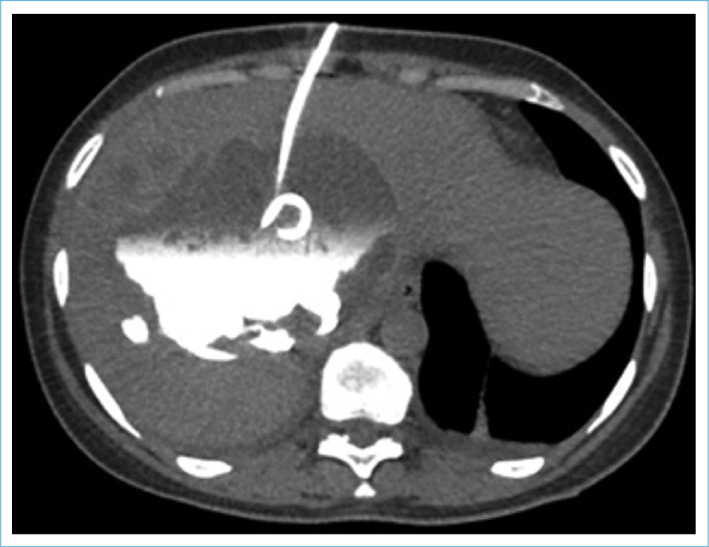

Biliary cystadenomas are uncommon lesions with clinical and radiological characteristics that overlap with other cystic liver lesions. Here, we intended to discuss a biliary cystadenoma found in a 37-year-old female patient who had been treated for a liver abscess and had been sent to our clinic with a long-term hydatid cyst diagnosis.

Abstract Image